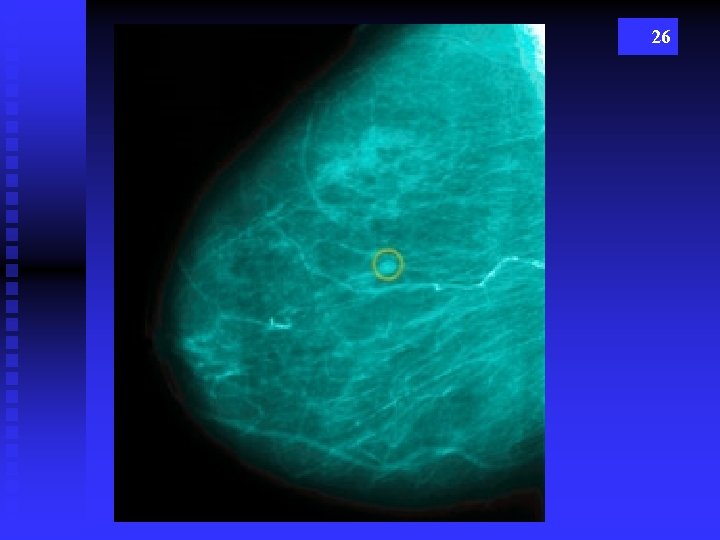

26